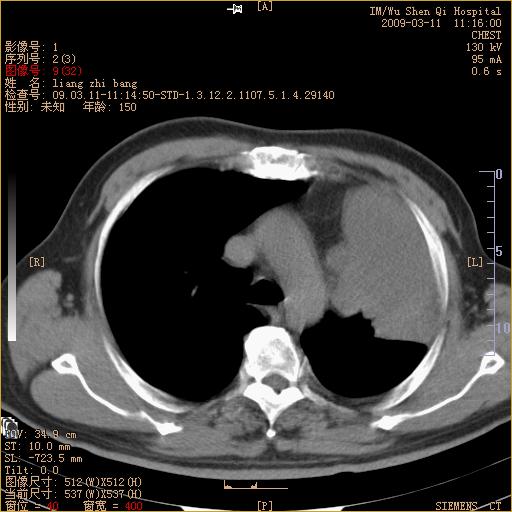

标题: CT18604:男,60岁,咳嗽一月余 [打印本页]

标题: CT18604:男,60岁,咳嗽一月余

1)考虑左肺上叶中央型肺癌并左肺上叶肺不张;建议必要时行纤支镜检查进一步明确诊断。2)左侧胸腔积液。

肺门肿块、支气管开口闭塞伴肺不张及胸水!典型的中心型肺癌变现!

1、左肺上叶中央型肺癌并上叶阻塞性肺不张。

2、左侧胸腔少量积液,右侧胸膜轻度增厚。

左肺们肿块并左肺上叶不张。考虑左肺中心性肺癌并左肺上叶不张及左侧胸腔积液